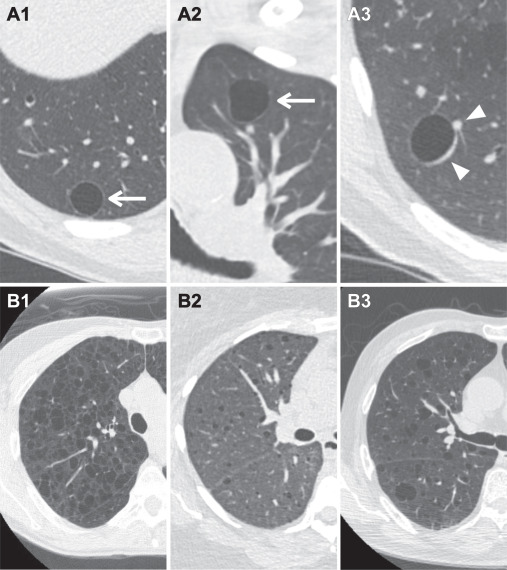

- Nang thành mỏng, được định nghĩa là nang đơn ngăn có độ dày thành < 2 mm, được coi là lành tính và không được phân loại hoặc quản lý trong Lung-RADS [27]. Nhiều nang phổi có thể gợi ý bệnh phổi dạng nang lan tỏa; tuy nhiên các tình trạng này không được phân loại trong Lung-RADS trừ khi xác định được nang có các đặc điểm đáng lo ngại (Hình 1).

Hình 1. Nang khí thành mỏng. (A) Ví dụ về nang khí thành mỏng đơn giản ở ba bệnh nhân (A1, A2, A3). Nang đơn giản là nang đơn ngăn với độ dày thành < 2 mm (mũi tên) và không được phân loại hoặc quản lý trong Lung-RADS. Cần cẩn thận để tránh nhầm mạch máu (đầu mũi tên) với nốt hoặc thành dày. (B) Ba bệnh nhân mắc bệnh phổi dạng nang khí: lymphangioleiomyomatosis (u cơ trơn bạch mạch – LAM) (B1), bệnh mô bào Langerhans (B2) và viêm phổi kẽ lympho bào (LIP) (B3). Bệnh phổi đa nang (Multicystic lung disease) không được phân loại hoặc quản lý trong Lung-RADS trừ khi nang được xác định có các đặc điểm không điển hình (ví dụ: nhiều ngăn, thành dày, có nốt đi kèm).